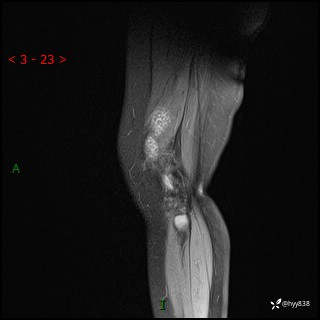

现病史:患儿1月前无明显诱因出现左下肢跛行,伴左膝关节红肿,无发热、咳嗽、恶心、呕吐等症,于当地医院就诊行X线片未提示异常,今至我院门诊就诊,门诊医师拟“跛行待查”收入院。 病后,患儿精神、食欲可,睡眠欠安,大小便通畅,体力体重无明显下降。

左膝MRI平扫